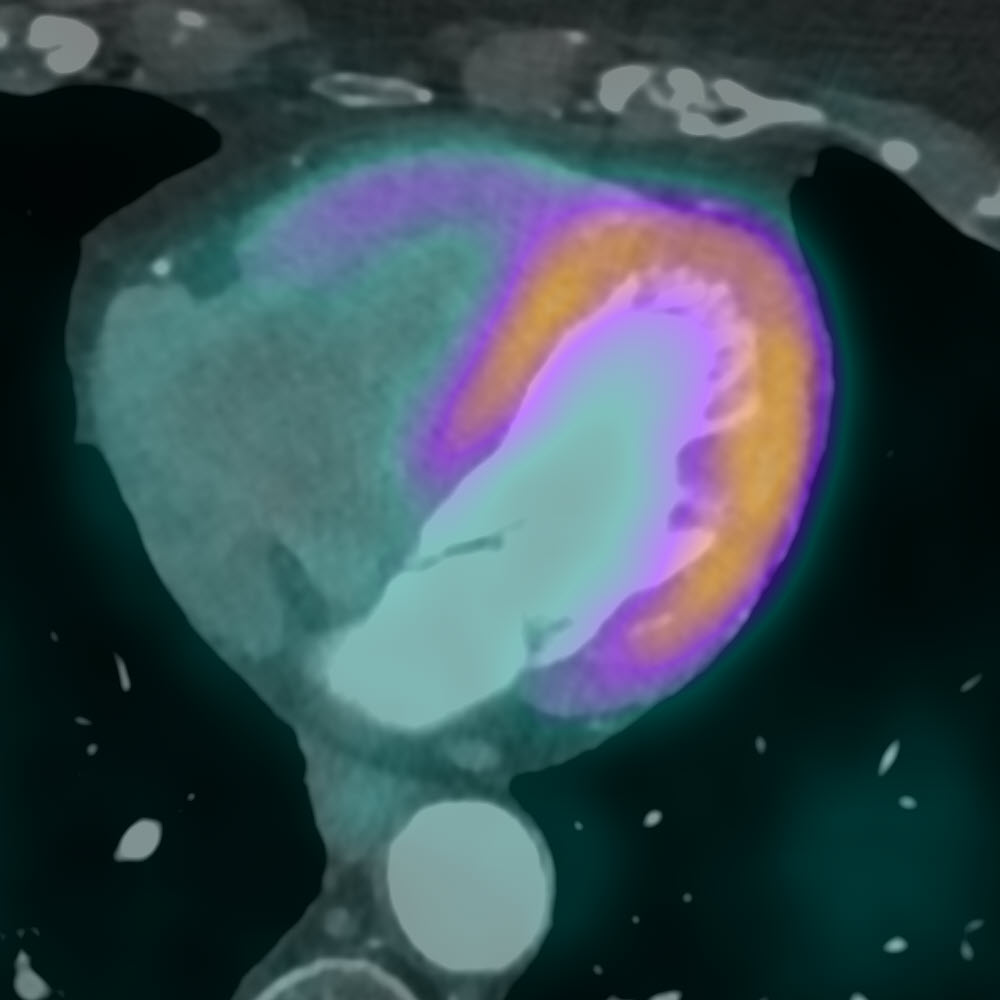

Fusion von PET und CT

Schicht-Rekonstruktion des Herzens mit Darstellung einer Kontrastmittel-gestützten CT-Untersuchung (links) sowie überlagert die Informationen zur Durchblutung des Herzmuskels (rechts, PET).

Evaluation der Herzfunktion

Erfassung der linksventrikulären Pumpfunktion